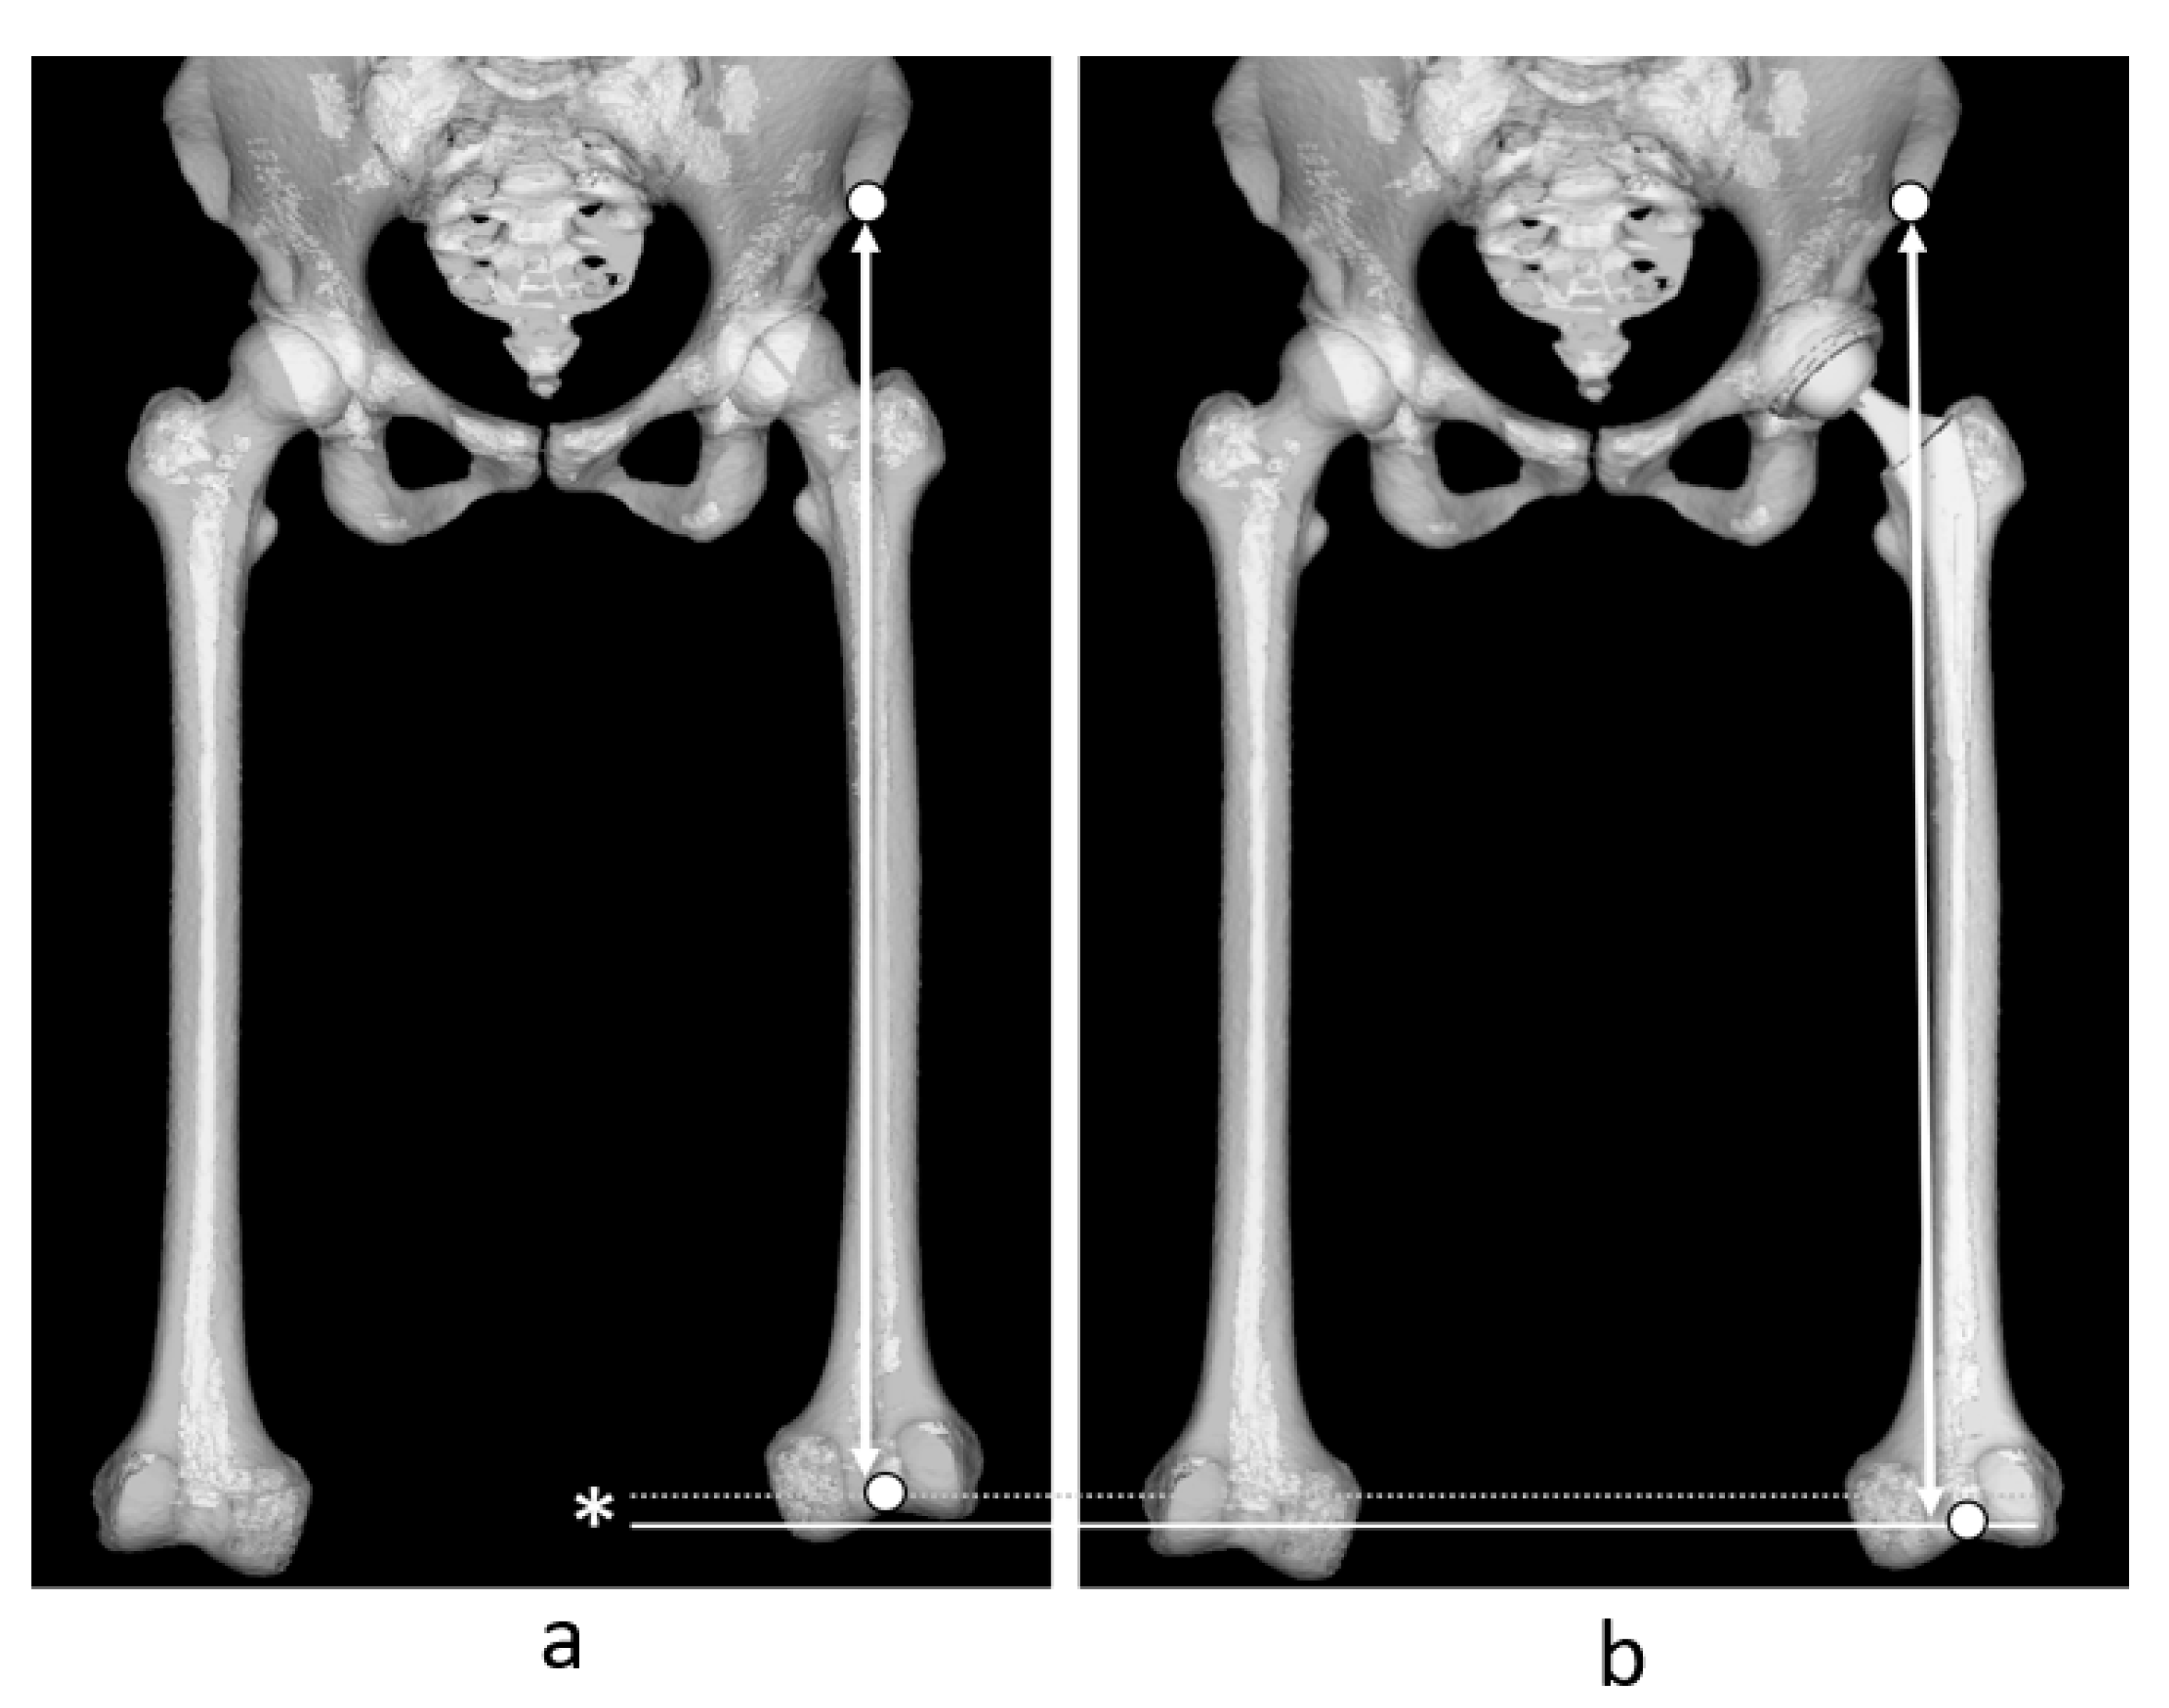

2.3. Measurement